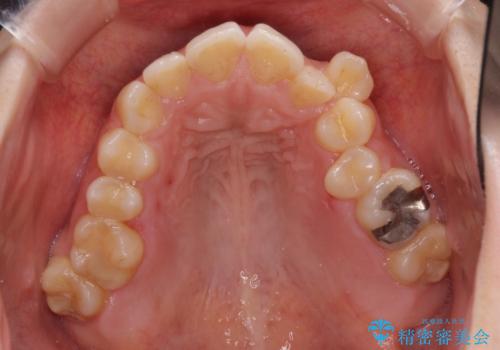

- 顕著な八重歯など、上下前歯のデコボコとスペースを気にして来院された患者様です。

八重歯改善には第一小臼歯の抜歯が必要であり、移動量が多いことから補助装置により八重歯を引き込むこととしました。

補助装置だけでなく、部分的にワイヤー矯正も使用しましたが、上下のスペースは改善しきれず、側切歯(前から2番目の歯)や顕著な八重歯は、インビザラインで治療するには限界があることがよく分かりました。

より良い仕上がりを希望される場合には、ワイヤー装置による矯正治療がお勧めとなります。